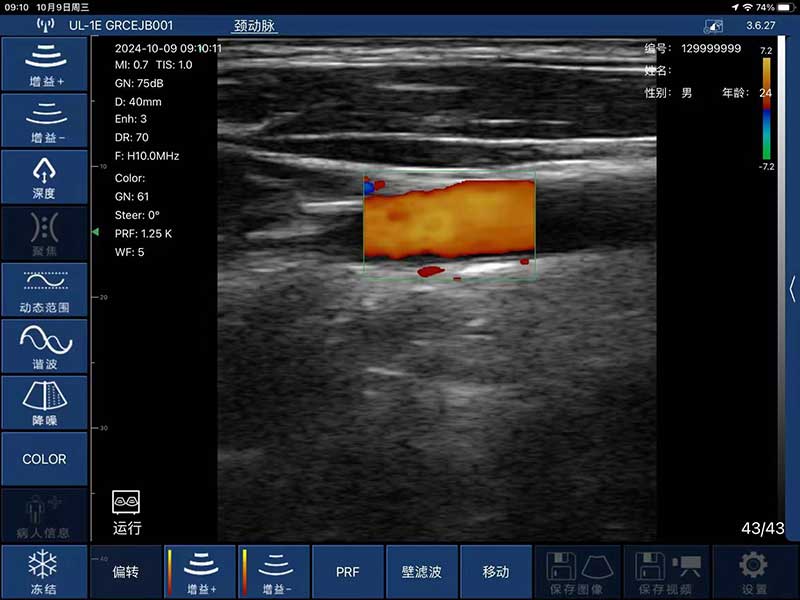

- 显示模式:B、B/M,Color、PW、PDI

- 探头频率:7.5MHz/10MHz

- 扫描深度:20/40/60/80mm

- 扫描宽度:40mm